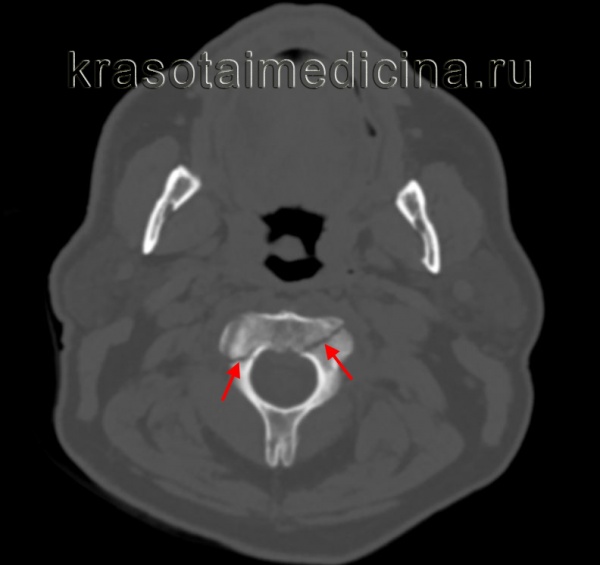

(Слева) КТ, аксиальный срез: взрывной перелом передней и задней дуг С1 с боковым расхождением фрагментов.

(Справа) КТ, аксиальный срез: симметричные переломы передней дуги С1, правой боковой части задней дуги и левой боковой массы, последняя линия перелома распространяется на отверстие поперечного отростка.